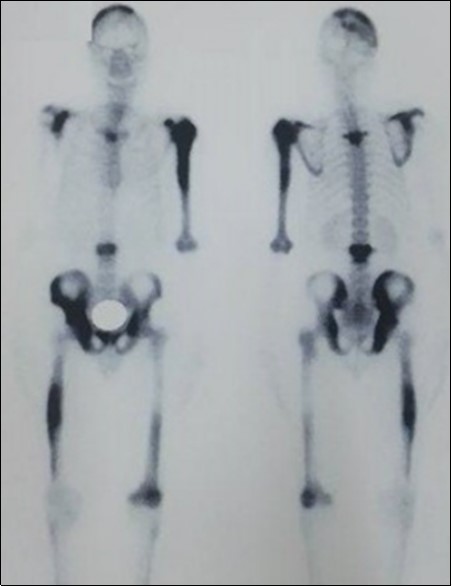

We report the case of an asymptomatic 49 years old male patient, in which a routine check objectified a biological cholestasis (gammagmutamytransferase = 2-3N and ALP = 5-6 N without hyperbilirubinemia or cytolysis). Nos past medical facts were noted. Abdominal ultrasound, viral markers and antibodies measurement (Ac Anti-nuclear, anti-Mitochondrial, anti-LKM1, Anti-cytoplasmic) were normal. Magnetic resonance choalngiopancreatography objectified multiple biliary strictures and parietal irregularities evocative of SC (Figure 1). Colonoscopy showed no associated inflammatory bowel disease. Patient received high doses of ursodeoxycholic acid (20mg/kg) for the SC with partial improvement of liver function but persistence of a marked rise in ALP level. In order to better characterize the nature of ALP, a dosage of ALP isoenzymes was performed and objectified a predominant bone fraction (83%), while liver fractions H1 and H2 were respectively of 12% and 4%. X rays objectified bone condensations with a fibrillar appearance and bone hypertrophy suggestive of PD (Figure 2). A bone scan made for lesions mapping showed a multifocal PD (Figure 3). The patient was treated by bisphosphonates (injections of zoledronic acid), which was associated with a decreasing in ALP level after 6 months.

Figure 3.Bone scan mapping lesions showing a multifocal achievement of the bones

Bone scan mapping lesions showing a multifocal achievement of the bones